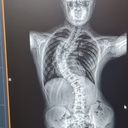

However, early 2023 we noticed some changes in his back/spine and was later diagnosed with Adolescent Idiopathic Scoliosis.

He has taken this in his stride but as you can see from the photo's, The bend in his spine has become quite extreme and he needs to have urgent surgery.